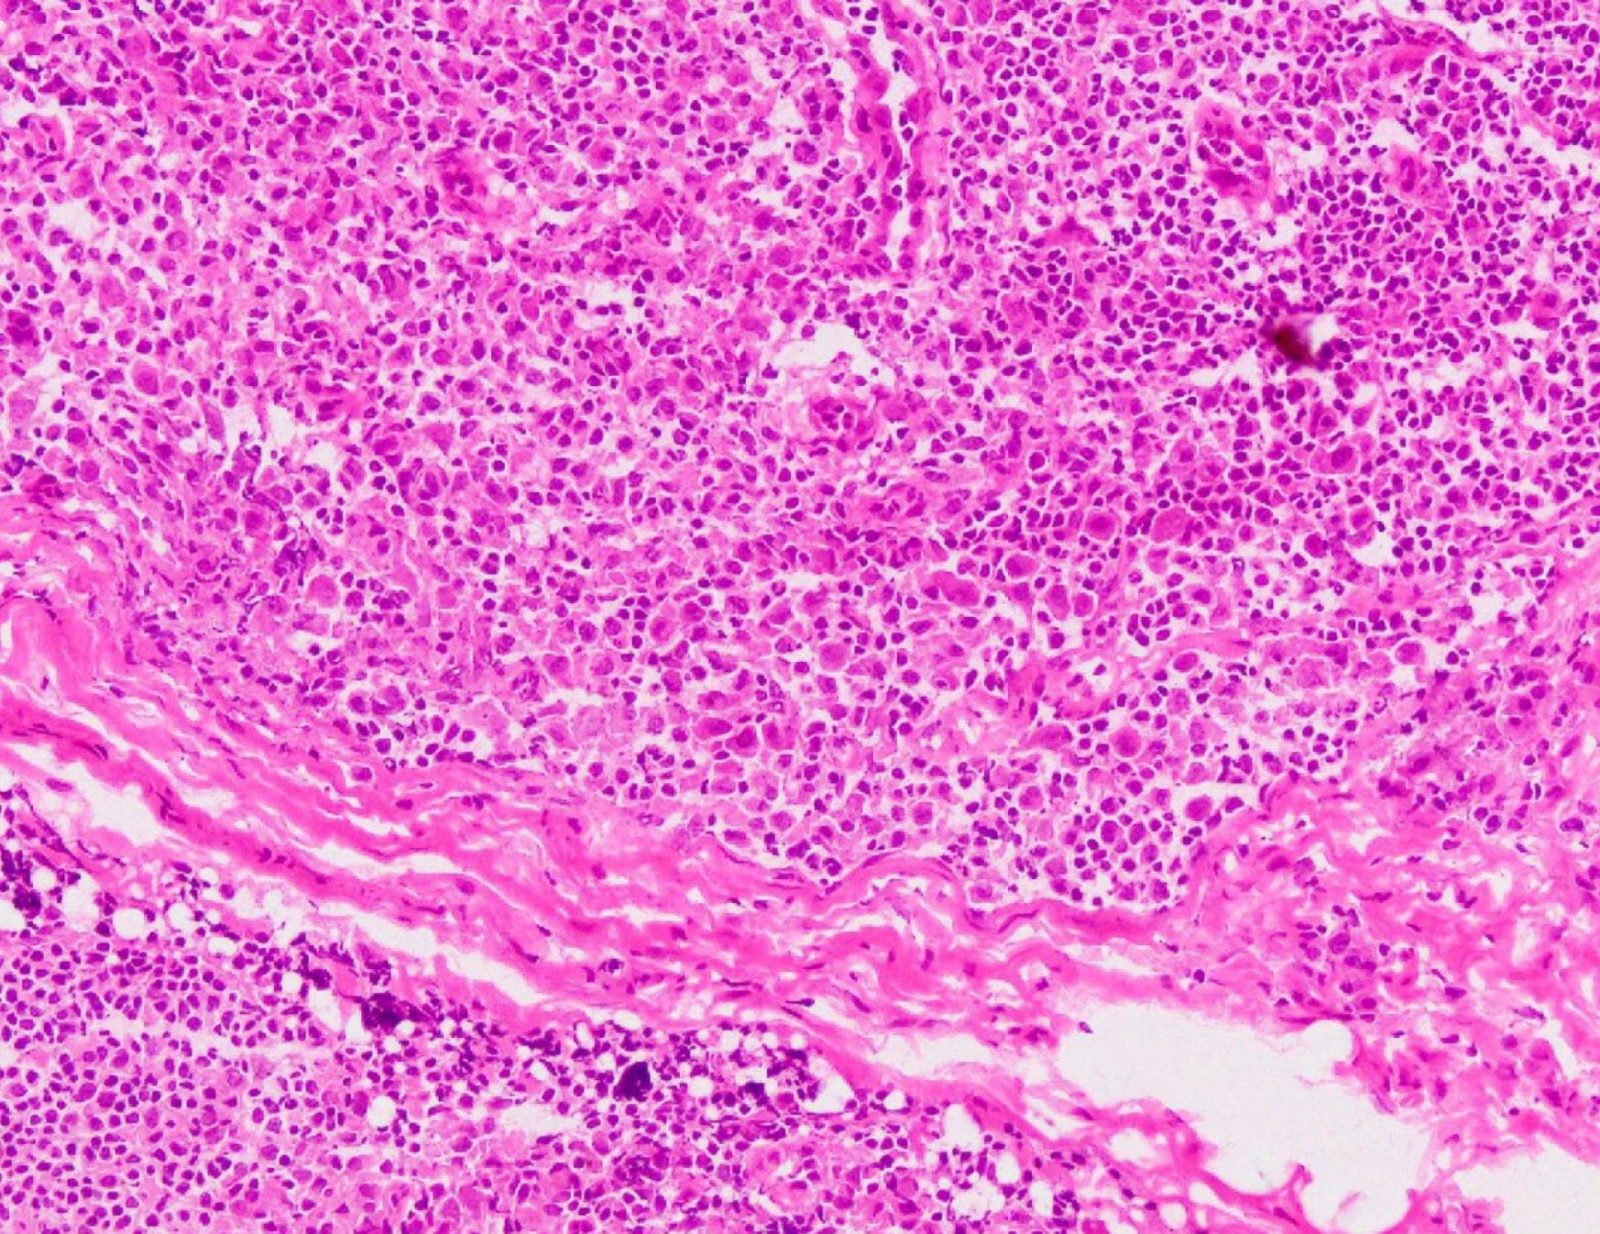

Among these, positive and negative cases in the remote consultations were 8 (18%) and 37 (82%), respectively. Compared to the permanent specimens, the overall accuracy ratio was 89% (40/45), with the positive and negative predictive values being 67% (6/9) and 94% (34/36). Supplementary table 1 shows breakdowns of cases where paraffin section and frozen section of sentinel lymph nodes differed. An illustrative example of these discrepancies is shown in Figure 1, where a false positive diagnosis occurred during a remote intraoperative frozen section consultation of a sentinel lymph node biopsy. Upon review of this case, it was determined that prominent histiocytic proliferation had been mistakenly identified as cancer cells.

We reviewed a total of four out of the five cases for which there were discrepancies between diagnosis of paraffin section and frozen section of sentinel lymph nodes. After the review, it was determined that there were no differences in diagnosis between the digital and traditional frozen sections of sentinel lymph nodes (Supplementary table 1). Furthermore, both the quality of the frozen sections and the images obtained from the monitor for the digital slides were excellent. There were no issues such as tissue wrinkles, tissue overlap, tissue folding or air entrapment in the microscopic preparation. There was no apparent difference in diagnostic accuracy between the two systems.

Figure 1: Microscopic image (hematoxylin–eosin stain) of extracted lymph node from case 1 (200× magnification).

Figure 1: Microscopic image (hematoxylin–eosin stain) of extracted lymph node from case 1 (200× magnification).